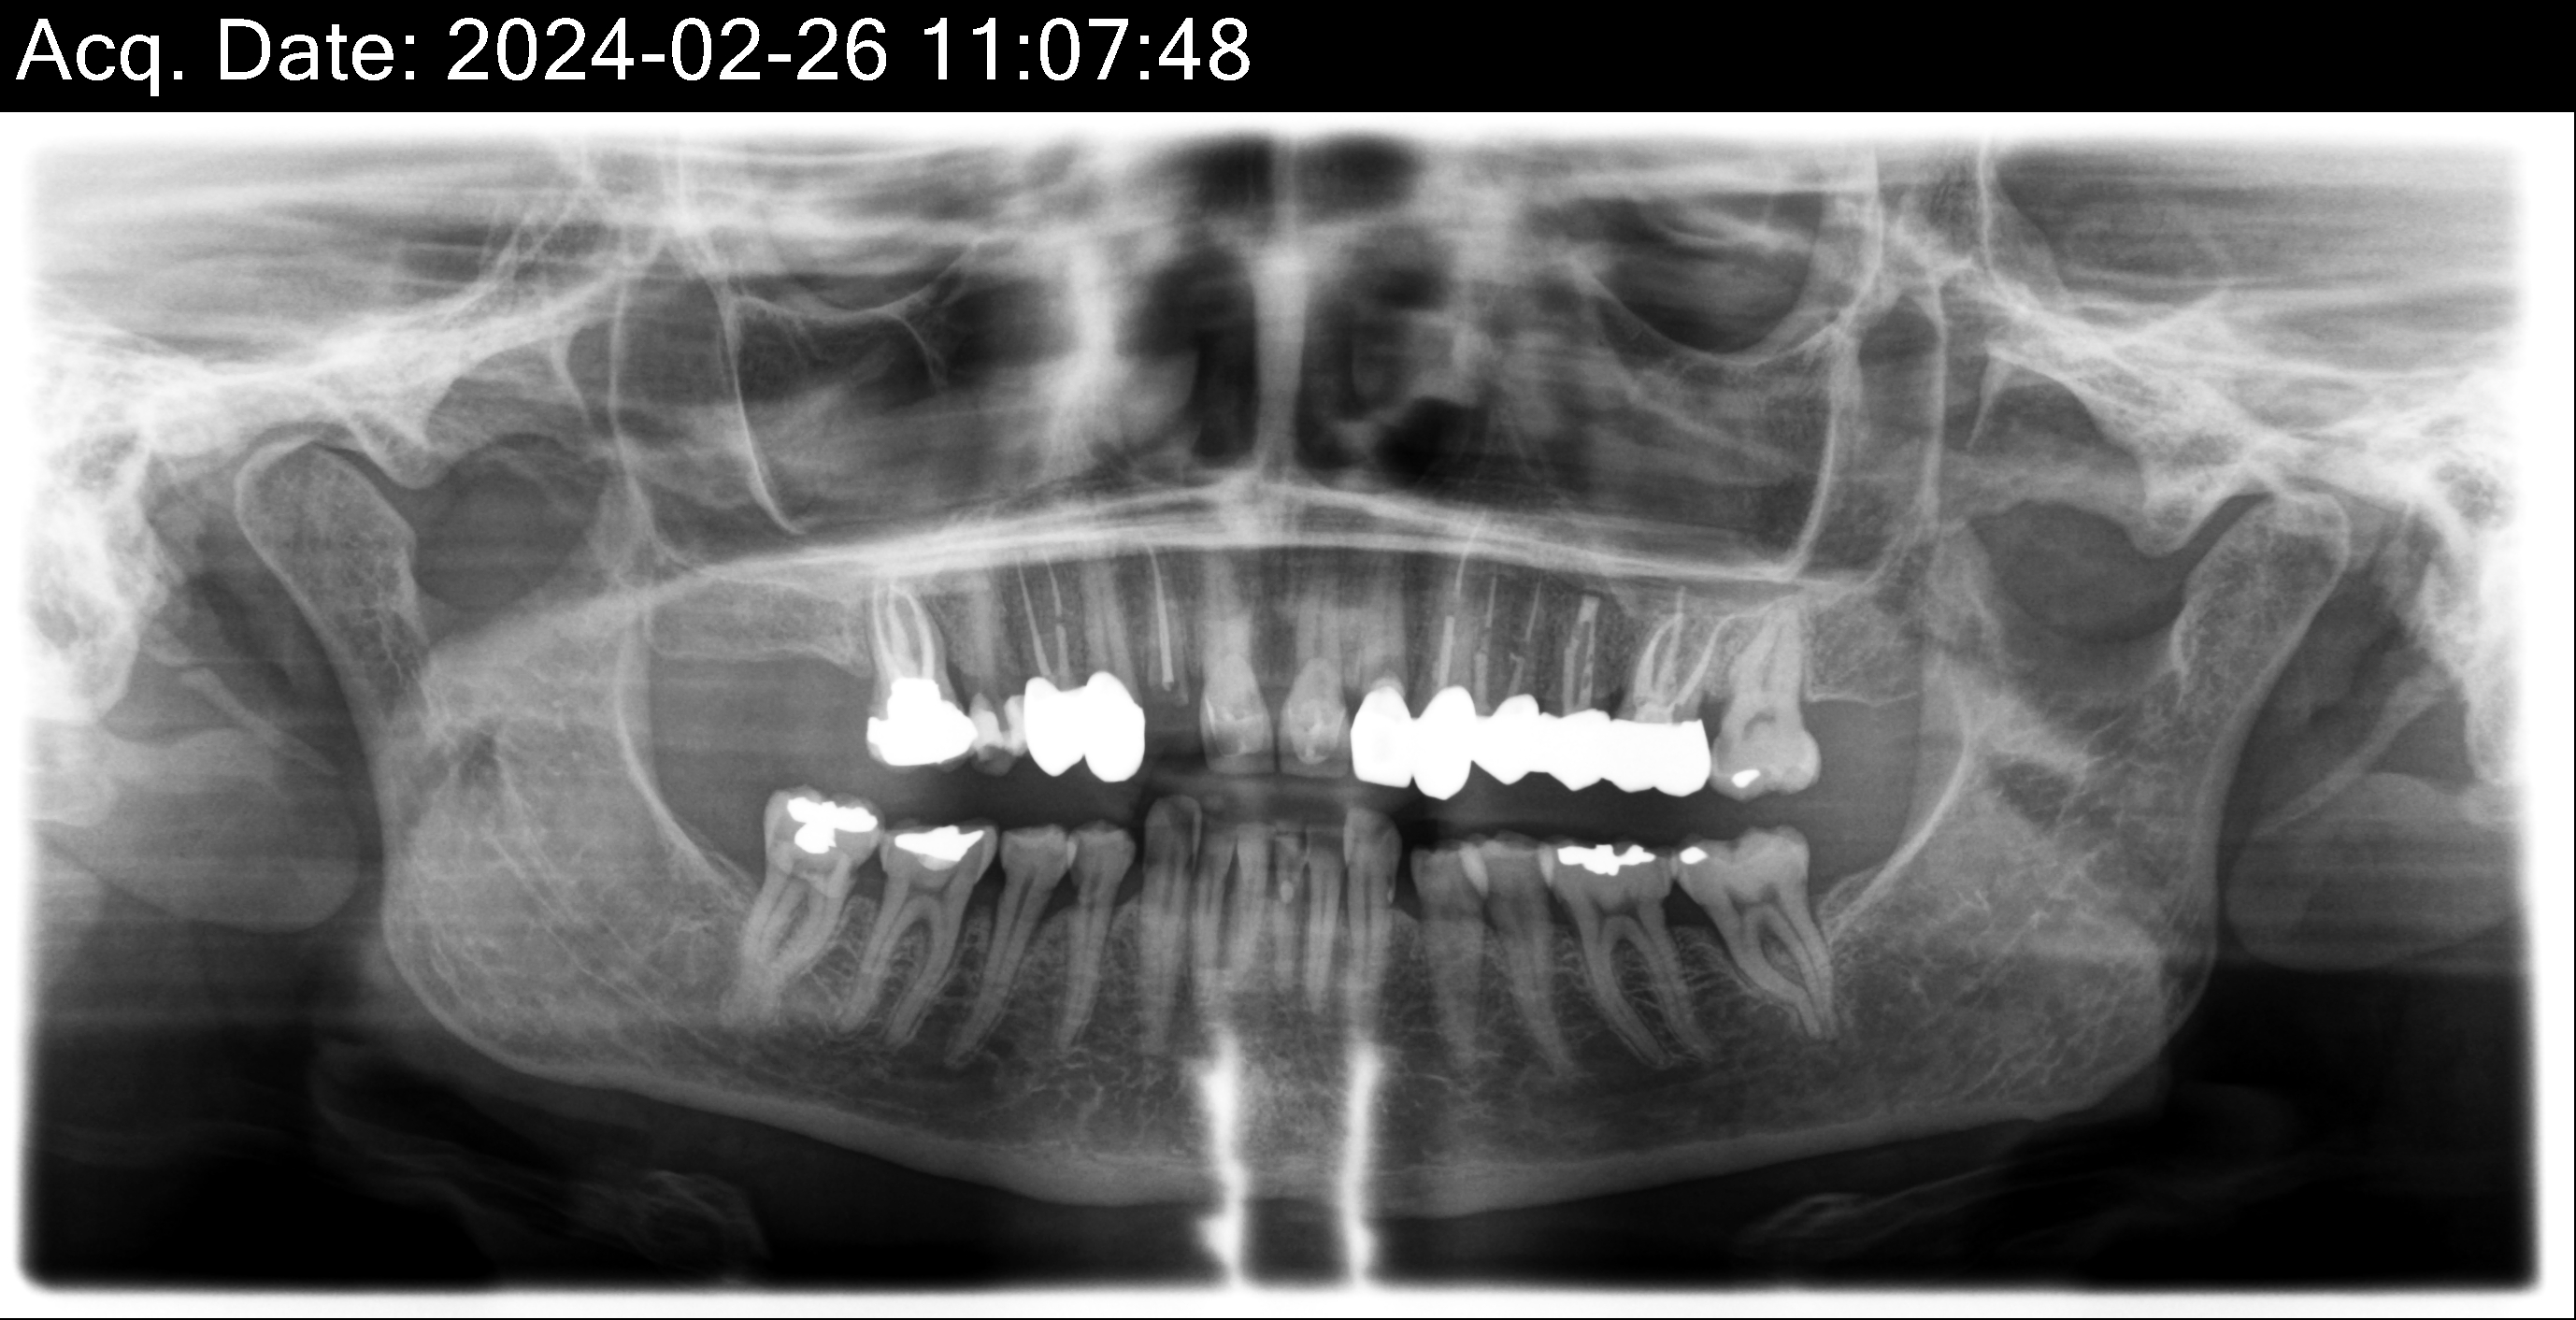

| Restorative | HY | HY | HY | HY | HY | HY | HY | HY | HY | HY | HY | HY | HY | HY | ||

| Surgical | X | X | X/IMP | X | X/IMP | X | X | X | X/IMP | X | X/IMP | X | X | X | ||

| Current situation | x | c | c | c | c | x | x | c | c | x | x | c | c | c | x | x |

| Tooth # | 1 | 2 | 3 | 4 | 5 | 6 | 7 | 8 | 9 | 10 | 11 | 12 | 13 | 14 | 15 | 16 |

| Tooth # | 32 | 31 | 30 | 29 | 28 | 27 | 26 | 25 | 24 | 23 | 22 | 21 | 20 | 19 | 18 | 17 |

| Current situation | x | c | c | x | ||||||||||||

| Restorative | HY | HY | HY | HY | HY | HY | HY | HY | HY | HY | HY | HY | HY | HY |

Overall information (upper arch)

12,13,14 have had root canals in past and now have quite a bit movement. 2-5 have all had root canals in past and now the crowns are breaking down.

Overall information (lower arch)

Overall, all of my gums have receded and most of the bottom teeth are exposed w/ some roots and there are many cavities.